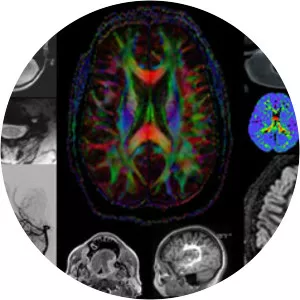

Neuroradiology is a subspecialty of radiology focusing on the diagnosis and characterization of abnormalities of the central and peripheral nervous system, spine, and head and neck using neuroimaging techniques.